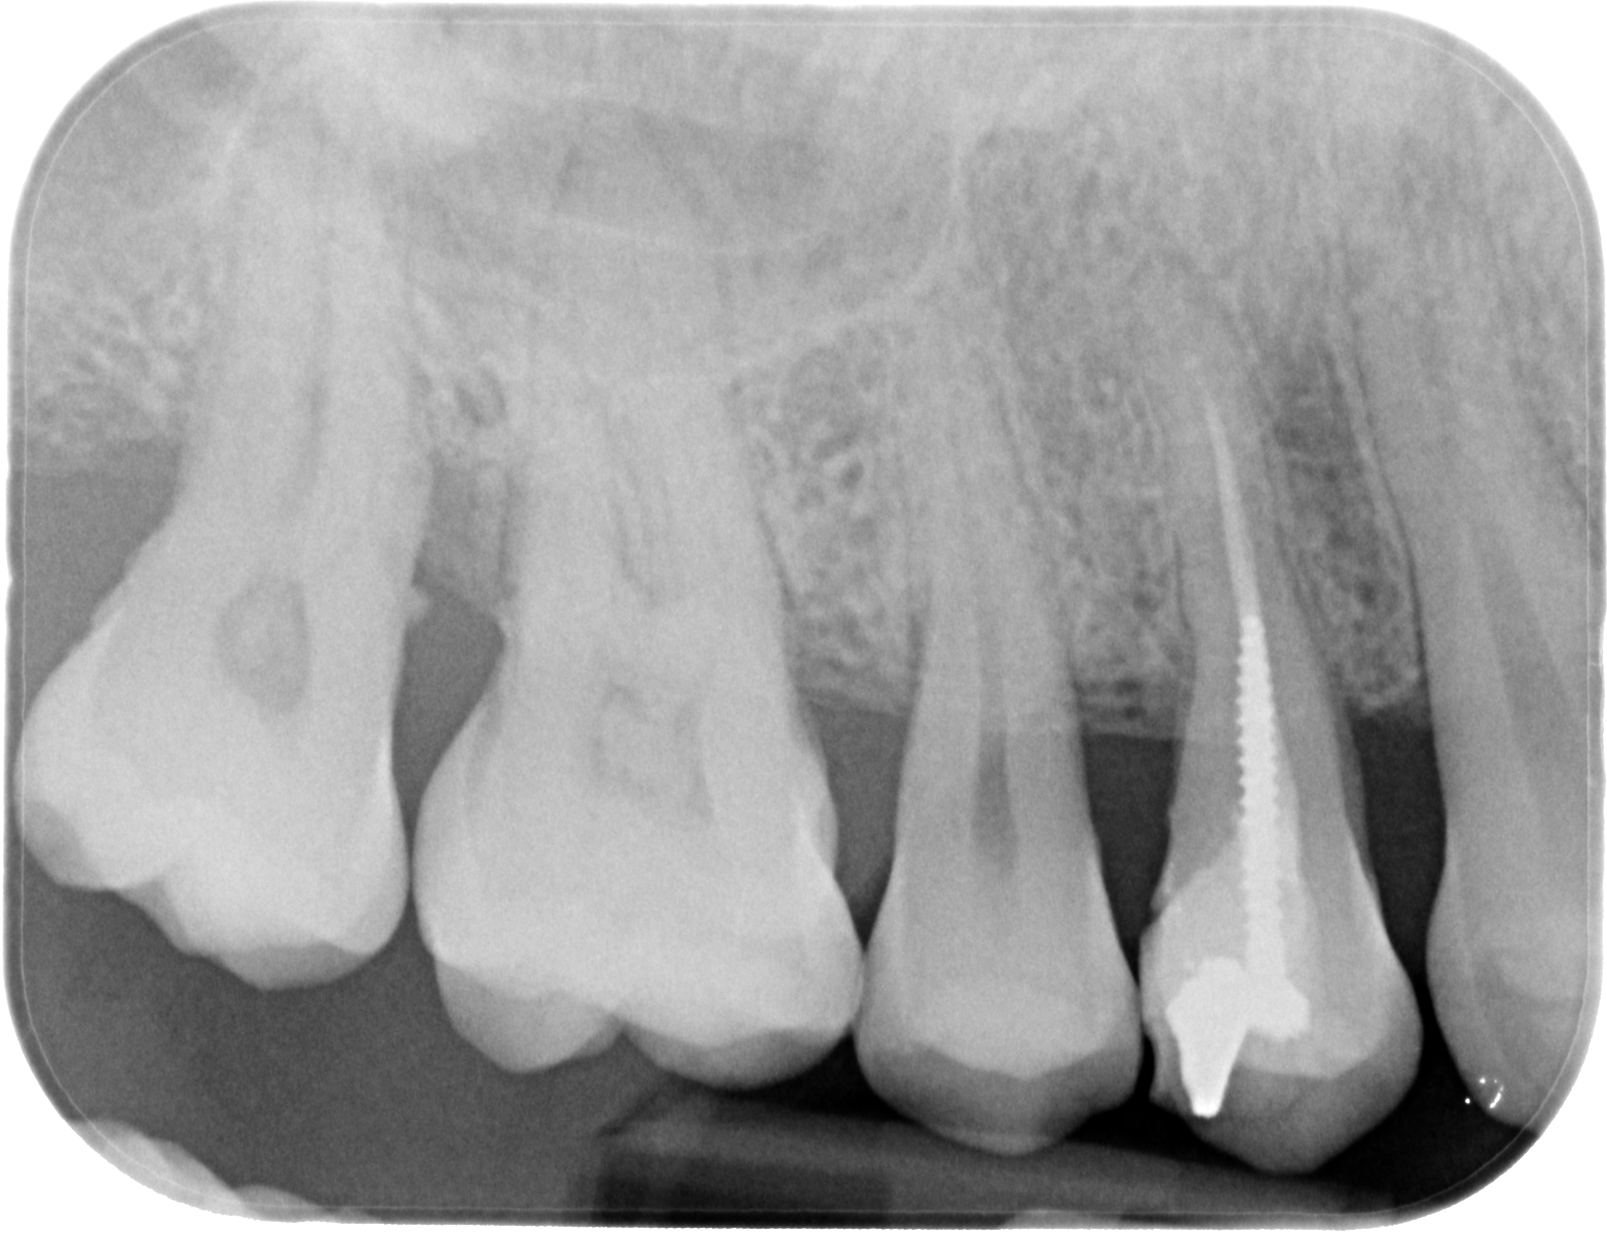

Fig. 02 : radiographie rétro-alvéolaire.